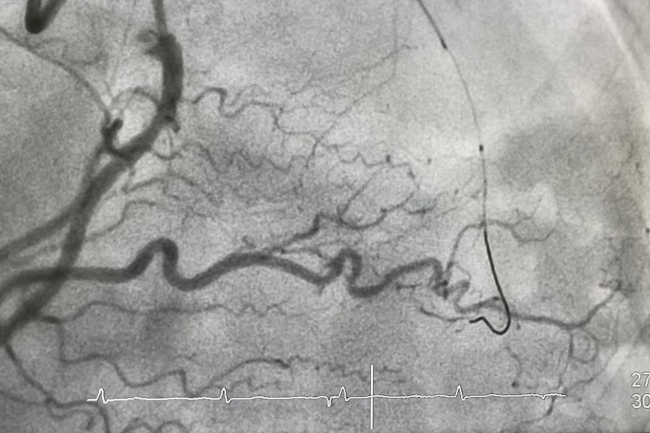

经导管辅件用于在患者的心血管系统中安全导航,以到达特定手术(如血管成形术、斑块切除术或瓣膜置换术)的目标位置。这些装置负责协助手术进入、在动脉路径中导航,并输送特定手术所需的器械和植入物。它们经过特别设计,具备多种尺寸和配置,以适应不同患者间多样的解剖结构差异,从而在各类心血管介入治疗中支持获得良好的治疗效果。

GlobalData 医疗事业部咨询高级总监 Charlie Whelan表示:“要更换一个主动脉瓣,导管需要通过患者手臂或腹股沟的穿刺口一路蜿蜒进入体内,直达心脏,而所经过的血管细得像意大利面一样。这样的导管须具备足够的可扭转性,能够弯曲和转向,有时甚至达到180度,同时不能对心脏系统或身体的其它部位造成任何损伤。”Charlie补充道:“因此,医疗器械行业的关注点,自然集中在能够让侵入性操作技术更加高效的创新上,从而减少手术中的创伤,并降低患者的风险。”